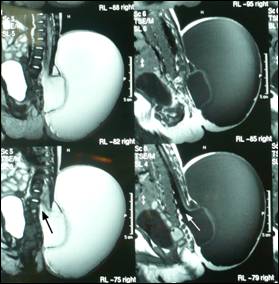

Figure 2: MRI sagittal section showing two cysts. The inner cyst

was in continuation (arrow) with the central canal of the spinal cord.

Figure 3: MRI in coronal section showing double compartment swelling.